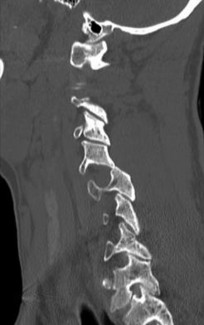

A 45-year-old male with a 20-year history of ankylosing spondylitis presents to the emergency department after a low-energy trip and fall at home. He complains of new-onset, severe lower cervical neck pain. Neurologic examination is unremarkable.

Standard AP, lateral, and odontoid plain radiographs are interpreted as normal. What is the most appropriate next step in management?

Explanation